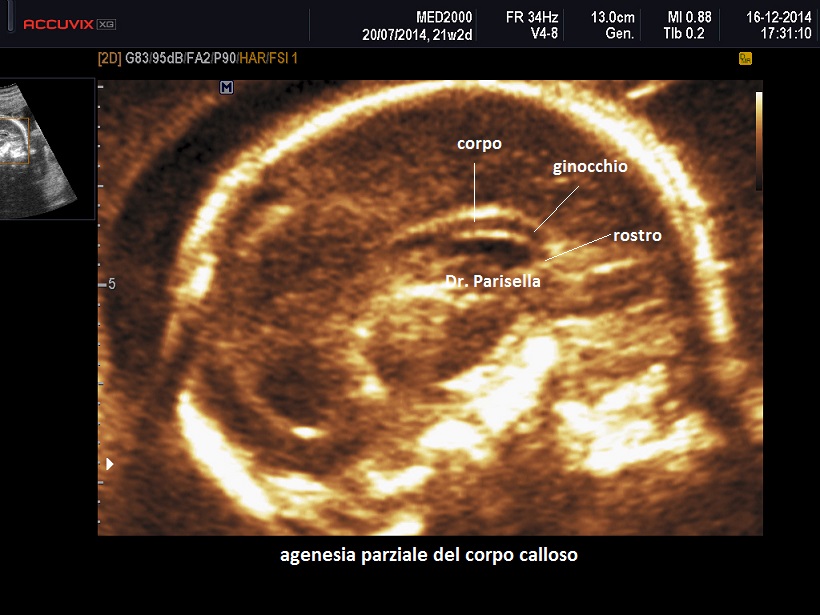

Con il termine agenesia complicata del corpo calloso legata all'X si definisce un fenotipo che viene considerato parte dello spettro clinico della sindrome L1; anch'essa è quindi legata a mutazioni del gene L1CAM che mappa in Xq28. E' caratterizzata da paraplegia spastica variabile, deficit cognitivo lieve-moderato e agenesia parziale o totale del corpo calloso.